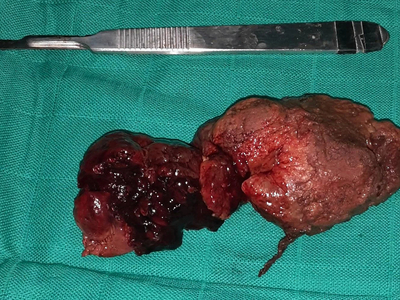

An “enormous” gossypiboma, which is a mass inside the body composed of retained surgical gauze or sponge surrounded by an inflammatory foreign body reaction.